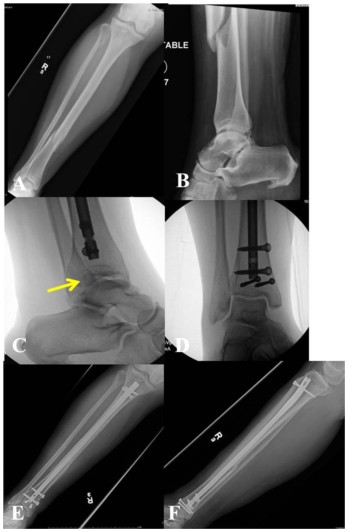

Сообщается о высоком проценте переломов нижней средней трети большеберцовой кости с переломами лодыжки. При использовании традиционной компьютерной томографии 43 % переломов средней и нижней трети большеберцовой кости сопровождались переломами голеностопного сустава, большинство из которых требовало хирургического лечения. Наиболее частым типом перелома был спиральный перелом нижней средней трети дистального отдела большеберцовой кости, связанный с переломом задней лодыжки с небольшим или несмещенным смещением (рис. 2). Из-за небольшого смещения связанного перелома лодыжки только 45 % повреждений можно обнаружить на обзорных рентгенограммах лодыжки. Таким образом, при наличии перелома нижней и средней части большеберцовой кости следует уделять особое внимание рутинному компьютерному сканированию голеностопного сустава (рис. 3).

Рисунок 2. AF Спиральный перелом нижней средней трети правой большеберцовой кости (A, B). На предоперационных рентгенограммах лодыжки все в норме (C). Интраоперационная рентгеноскопия на С-дуге показывает перелом задней части лодыжки без смещения (D). Послеоперационные рентгенограммы после хирургической фиксации (EF) показывают плавное заживление переломов большеберцовой кости и лодыжки.

Рисунок 3. Спиральный перелом AF средней и нижней трети левой большеберцовой кости (AB) на предоперационных рентгенограммах; (CD) предоперационная КТ, показывающая перелом задней лодыжки без смещения; (EF) демонстрирует плавное заживление перелома большеберцовой кости и лодыжки.